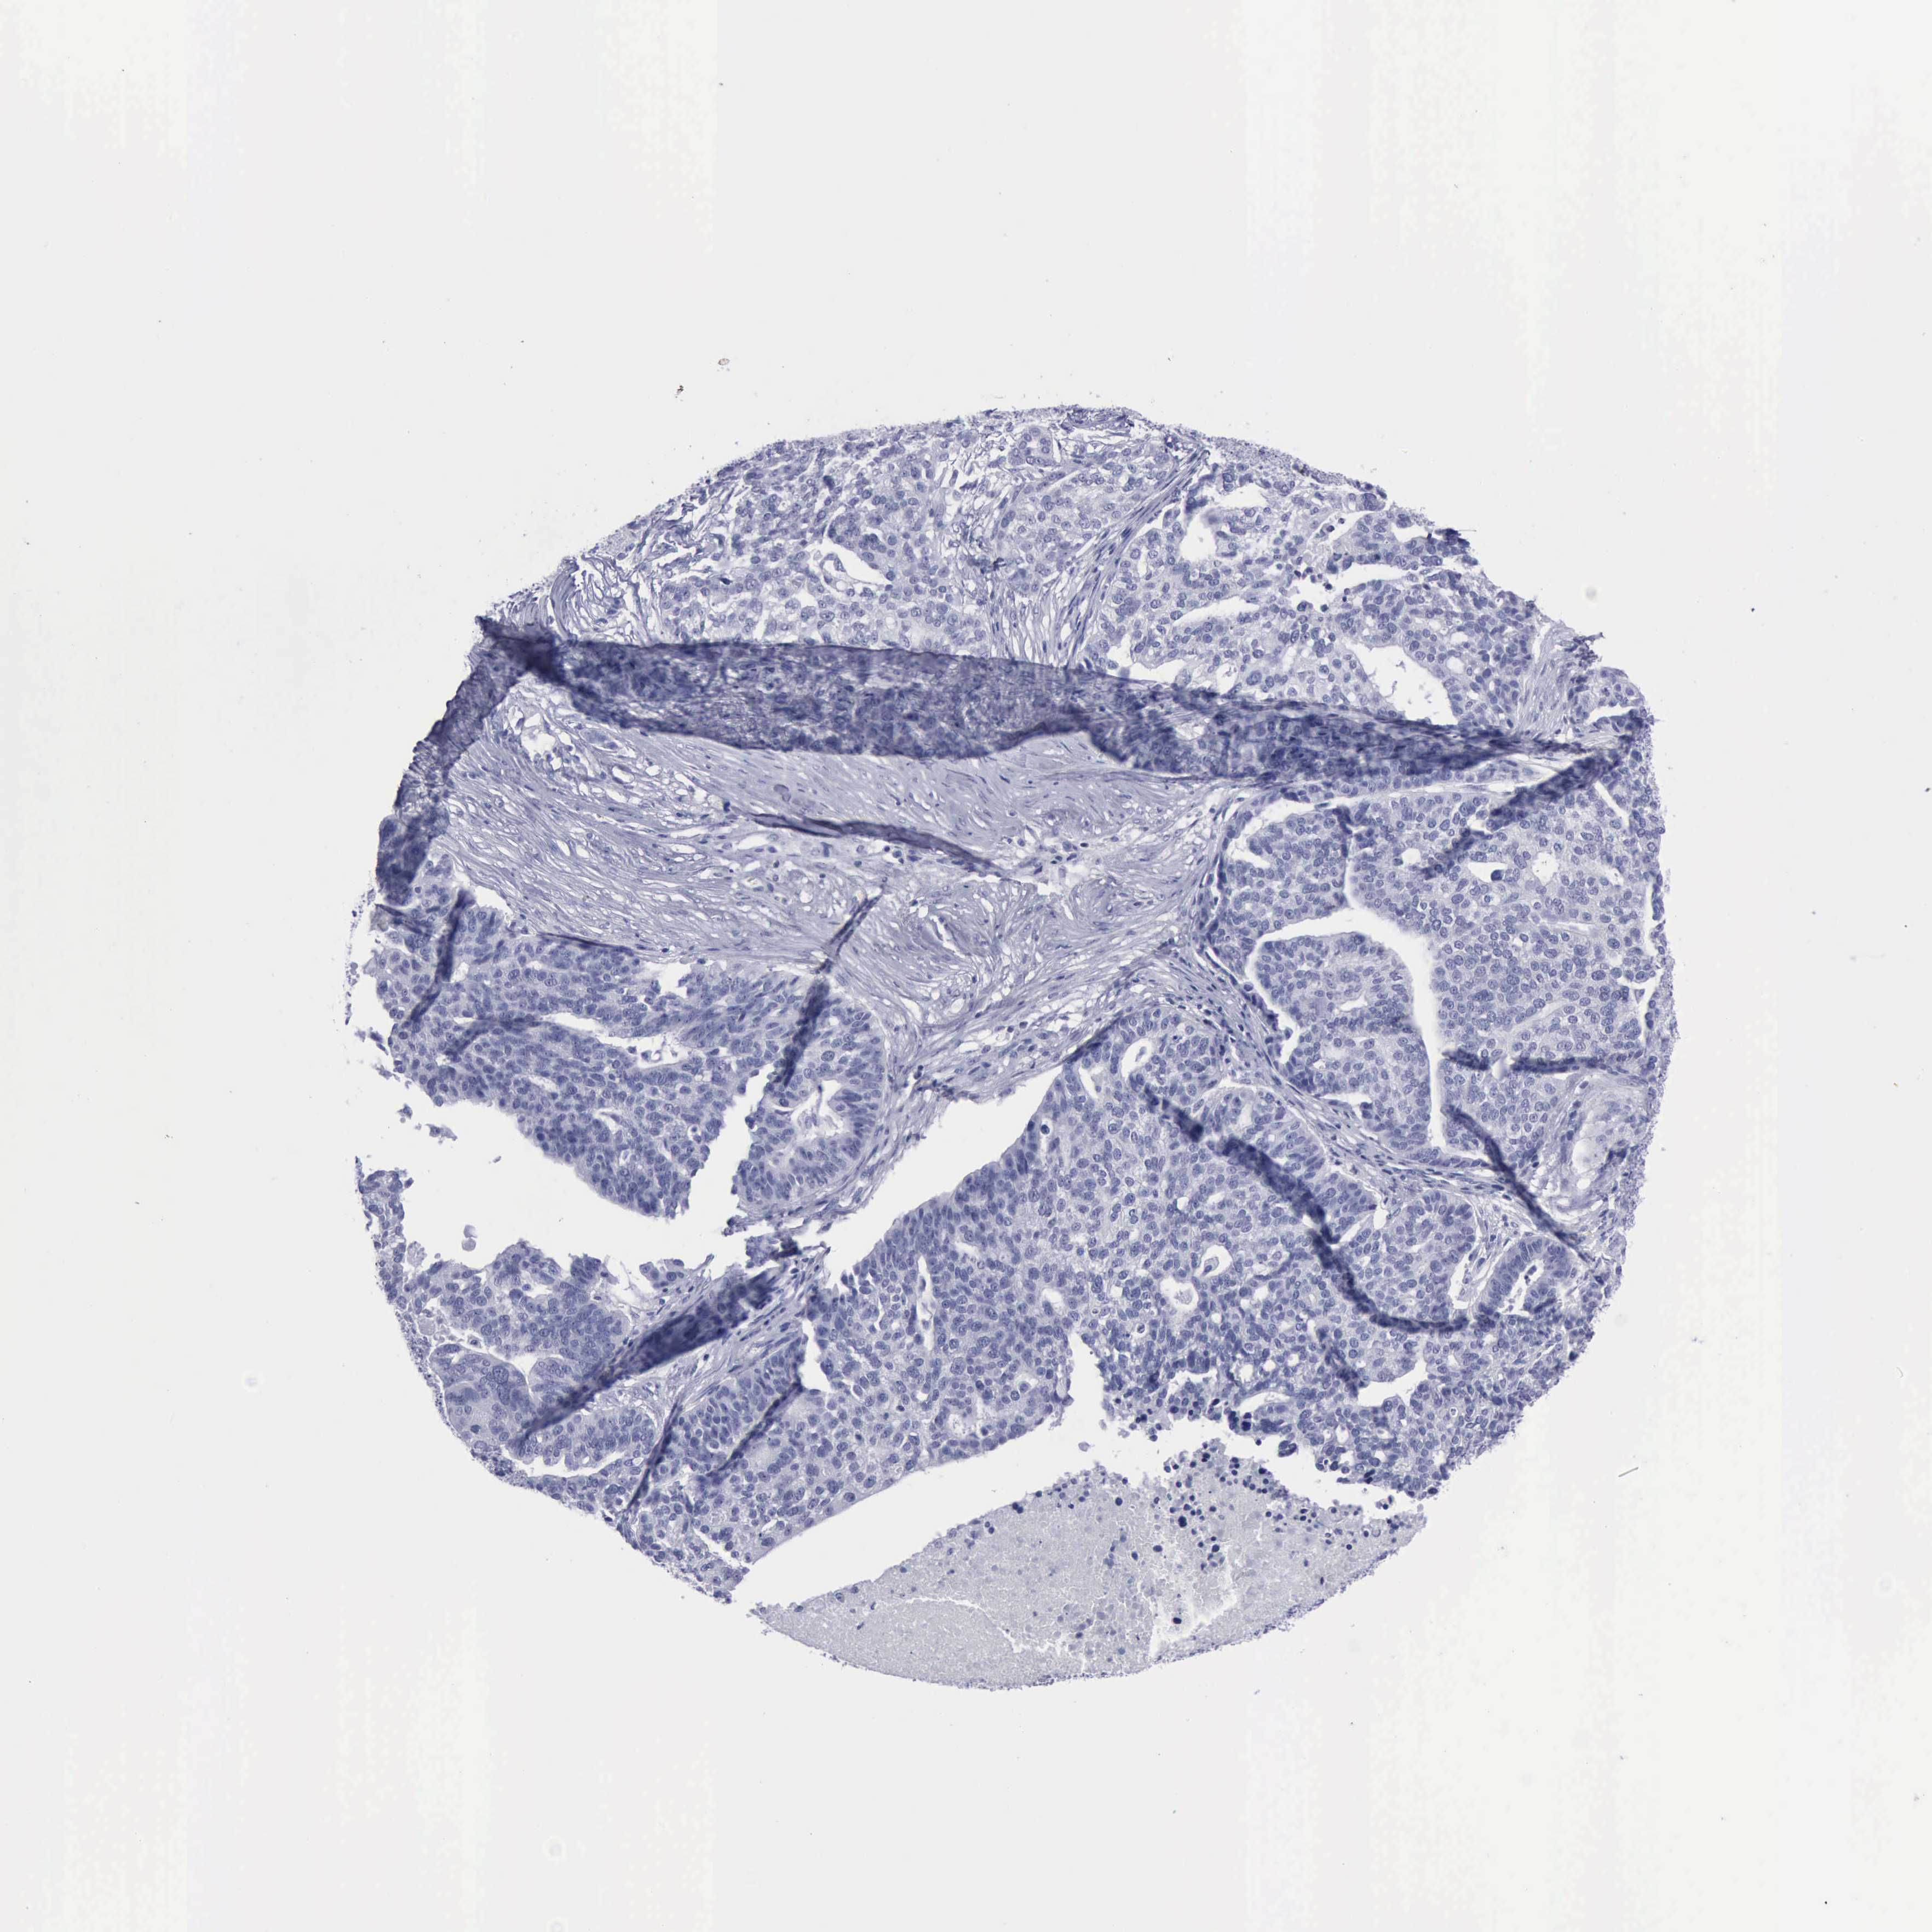

OVARIAN CANCER - Protein expressioni

A mouse-over function shows sample information and annotation data. Click on an image to view it in a full screen mode. Samples can be filtered based on level of antibody staining by selecting one or several of the following categories: high, medium, low and not detected. The assay and annotation is described here.

Note that samples used for immunohistochemistry by the Human Protein Atlas do not correspond to samples in the TCGA dataset.

Antibody stainingi

Antibody staining in the annotated cell types in the current human tissue is reported as not detected, low, medium, or high, based on conventional immunohistochemistry profiling in selected tissues. This score is based on the combination of the staining intensity and fraction of stained cells.

Each image is clickable and will lead to virtual microscopy that enables deeper exploration of all samples and also displays staining intensity scores, fraction scores and subcellular localization as well as patient and tissue information for each sample.

Antibody HPA030877

Antibody CAB000133

Staining

High

Medium

Low

Not detected

Intensity

Strong

Moderate

Weak

Negative

Quantity

>75%

75%-25%

<25%

None

Location

Nuclear

Cytoplasmic/membranous

Cytoplasmic/membranous,nuclear

Cystadenocarcinoma, serous, NOS

Carcinoma, NOS

Cystadenocarcinoma, mucinous, NOS

Carcinoma, endometroid